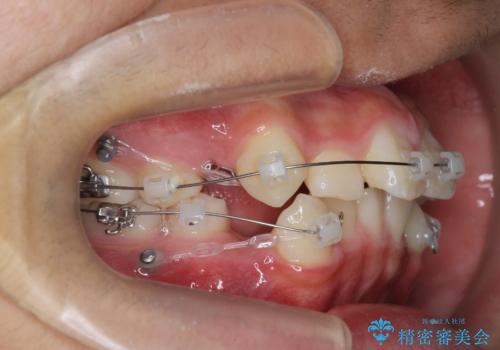

- 前歯のがたつきが原因で歯ブラシしづらい、見た目を改善したい!と矯正治療を希望され来院されました。

スペースの不足が見られるため、小臼歯の4本抜歯を行いマルチブラケットを用いた矯正治療を計画します。

噛み締めが強く、治療に時間がかかりましたが矯正治療の仕上がりに満足いただくことができました。